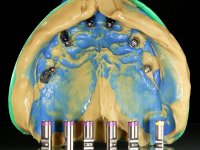

Realizada uma TAC, foi planificada a colocação de 6 implantes no maxilar superior. Foi decidida a colocação de dois implantes na zona dos incisivos centrais, dois implantes na zona dos caninos e dois na zona dos segundos pré-molares. A ausência de estrutura óssea na zona distal do primeiro quadrante implicava a realização de uma regeneração óssea no seio maxilar direito. A cirurgia foi realizada e após a colocação dos implantes foi feita a impressão para confeção de uma prótese provisória metalo-acrílica aparafusada para colocação em carga imediata no dia seguinte. O implante colocado na zona do seio maxilar direito não foi colocado em carga. Passados 6 meses foi realizada a impressão aos 6 implantes com técnica de moldeira aberta e foram confecionados os modelos de trabalho. Numa consulta seguinte foram montados os modelos de trabalho em articulador semi-ajustável utilizando o arco facial e a relação inter-maxilar obtida com a prótese provisória. Foi feita uma muralha de silicone sobre a ponte provisória com o objetivo de orientar o trabalho laboratorial. Realizada a infra estrutura metálica aparafusada esta foi provada em boca e finalmente após colocação de cerâmica o trabalho foi colocado definitivamente. Como passaram vários meses após a realização da primeira TAC foi feita uma segunda para planificar a colocação de implantes no 4º quadrante. Colocaram-se 3 implantes na mesma sessão em que foi feita a extração dos pilares da ponte. Estes implantes foram posteriormente reabilitados com uma ponte metalo-cerâmica aparafusada de três elementos.